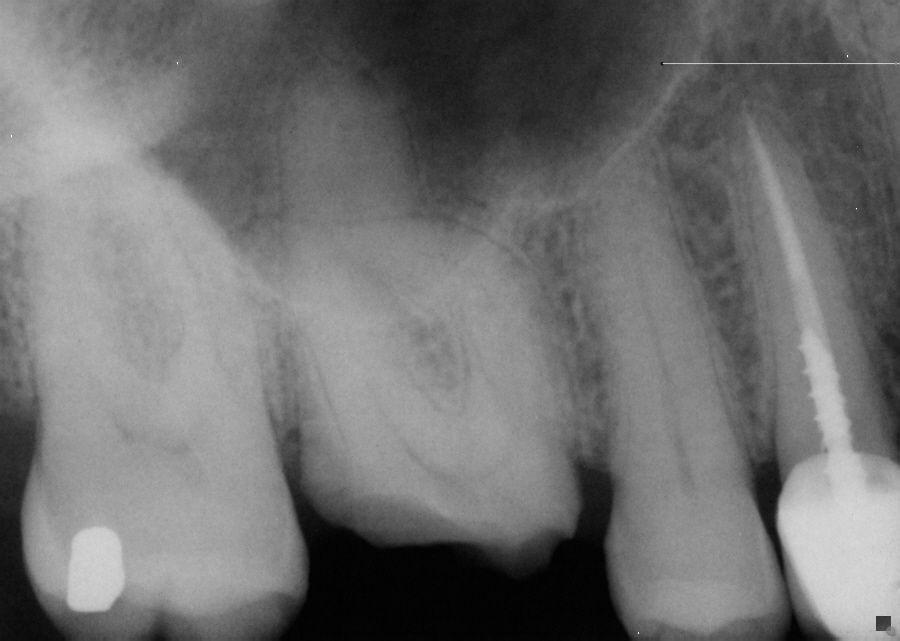

This is a root canal for a first maxillary molar (tooth #3) where an old crown (over 10 year old crown) fell out due to decay around the margin. As you can see there was a very curved canal which required additional time for proper root canal treatment. This tooth will now be restored with a post and crown allowing the patient to keep the tooth.